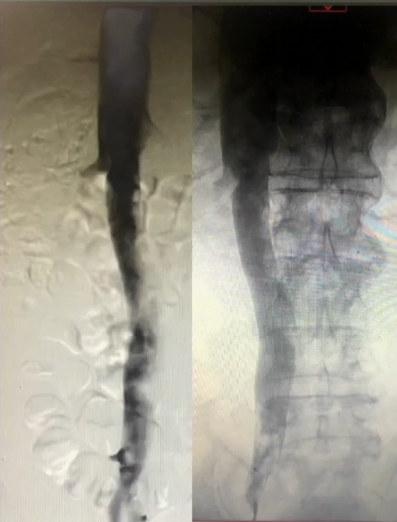

手术过程(一):局麻下,6F穿刺鞘穿刺右侧股静脉,造影见右肾静脉于第一腰椎下缘平面汇入腔静脉。换鞘后,引入腔静脉滤器,于第二腰椎上缘水平释放。

手术过程(二):8F鞘穿刺左侧腘静脉,造影见股浅静脉内充盈缺损,血液回流速度慢,髂外静脉内大量充盈缺损,髂总静脉未见显影,周围侧支循环开放。